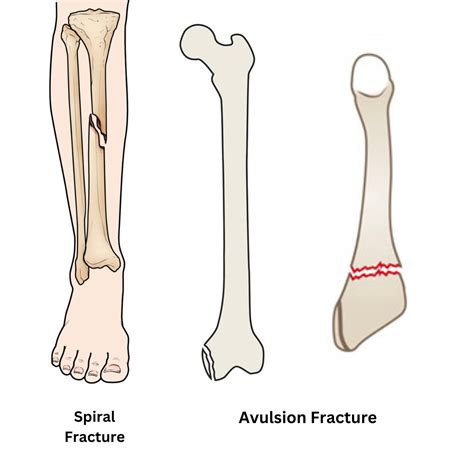

A transverse fracture is characterized by a clean break across the bone, perpendicular to its longitudinal axis. This type of fracture is commonly seen in long bones such as the femur, tibia, and humerus. The mechanism of injury typically involves a direct blow or a high-impact force, such as a fall from a height or a motor vehicle accident.

Case Study 1: A 30-year-old athlete sustains a transverse fracture of the tibia during a soccer match. The fracture is diagnosed through X-rays, and the athlete undergoes surgical treatment with ORIF. Post-operative rehabilitation includes physical therapy to restore strength and mobility.

Case Study 2: An 80-year-old woman falls in her home and suffers a transverse fracture of the femur. The fracture is treated non-surgically with a hip spica cast. The patient undergoes physical therapy to regain mobility and prevent future falls.

Case Study 3: A 10-year-old child falls from a playground equipment and sustains a transverse fracture of the radius. The fracture is treated with a cast, and the child is closely monitored to ensure proper healing and growth.